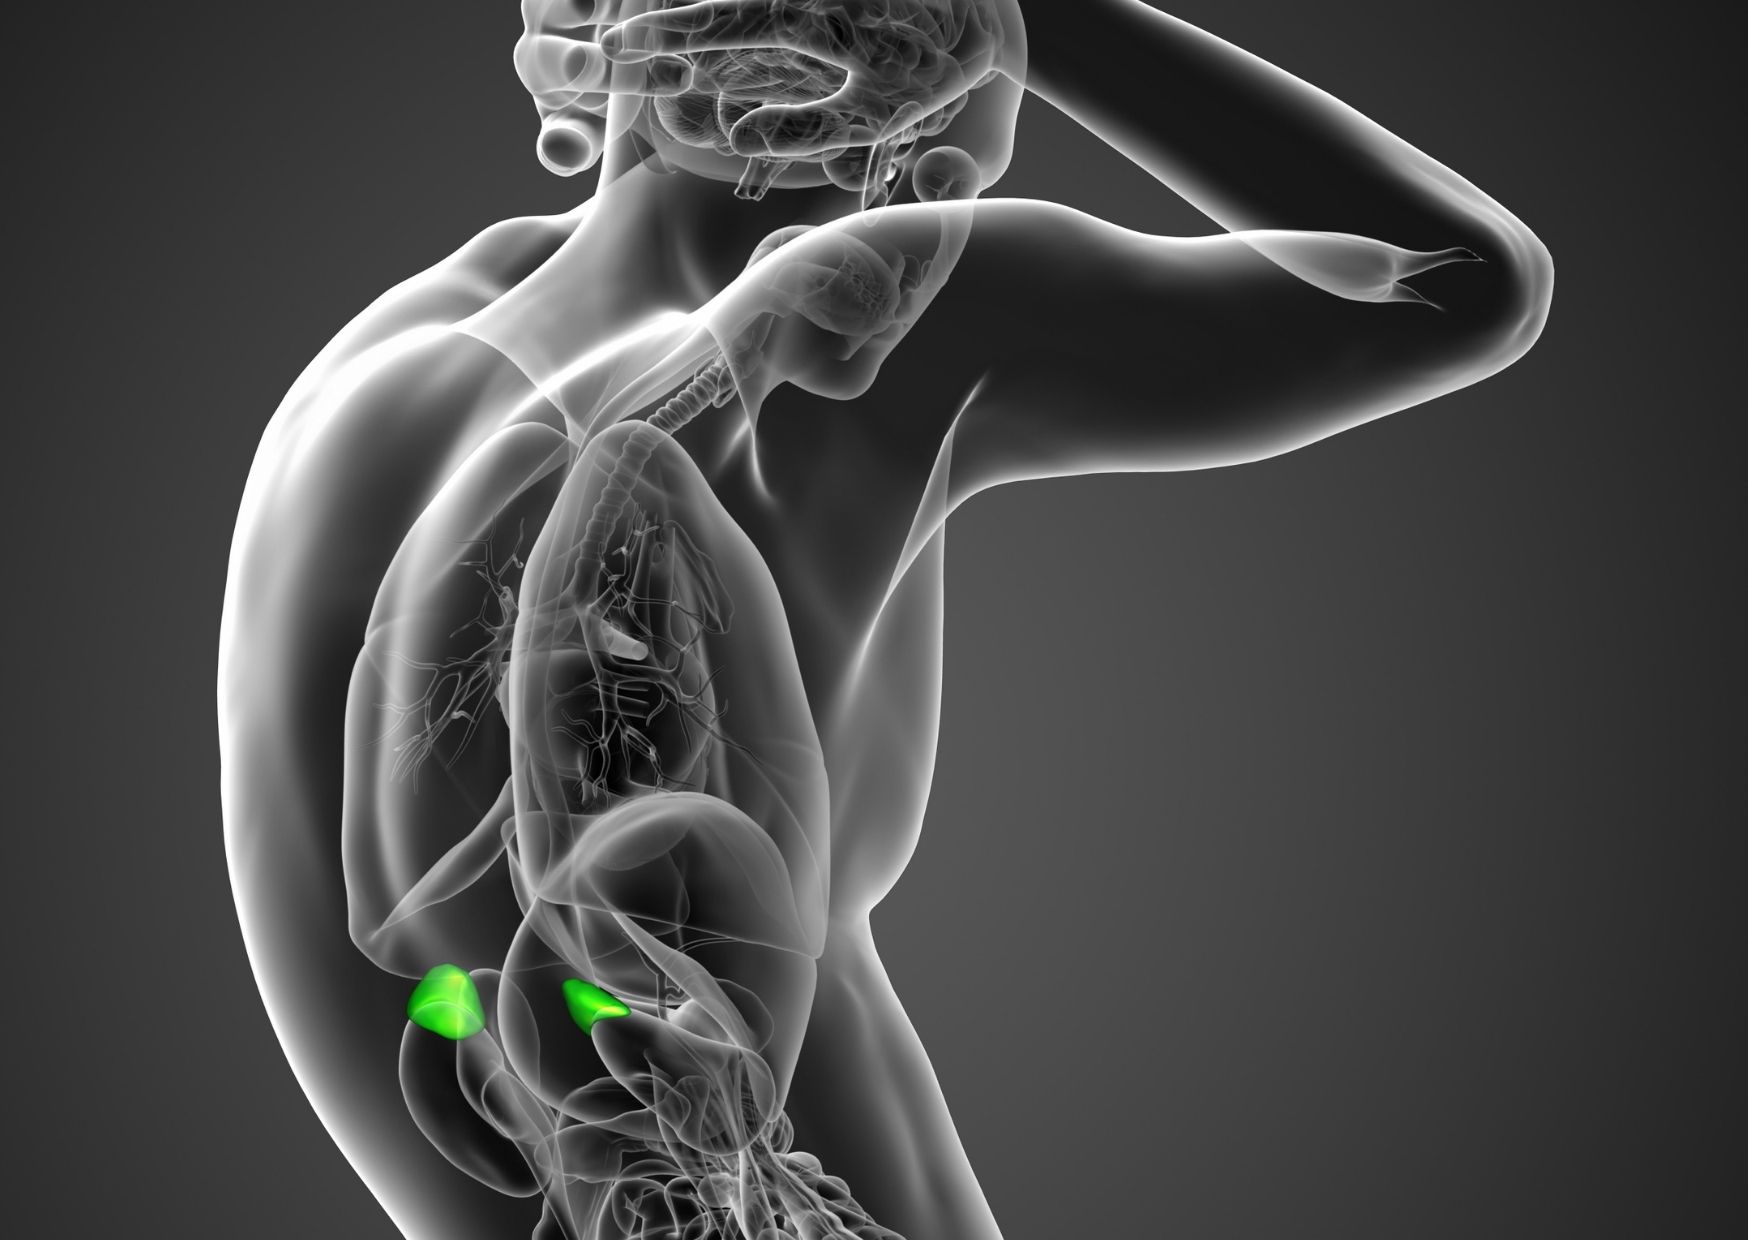

Adrenal glands are located on top of the kidneys